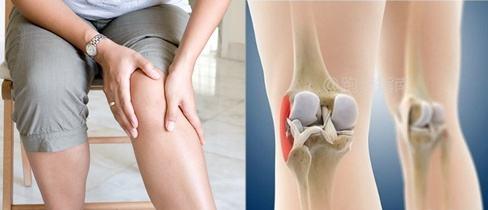

Le genou de course se caractérise par des symptômes typiques, il ne s'agit pas d'une dégénérescence du genou, ni d'une lésion du ménisque, c'est comme ça - marcher va bien, courir pendant une courte période, puis il y a une douleur et une difficulté près de l'extérieur du genou, passer à la marche, les symptômes disparaissent, puis dès que l'on court, la douleur revient, ce qui entraîne l'impossibilité de pratiquer le sport de la course à pied !

Le principal symptôme du genou du coureur est l'apparition progressive d'une douleur à l'avant du genou, autour de la rotule, qui s'aggrave lorsque l'on reste assis pendant une longue période ou que l'on monte ou descend des escaliers. En effet, lors d'une position assise prolongée, le muscle quadriceps tire sur la rotule, forçant celle-ci à entrer en contact avec le fémur. En montant et en descendant des escaliers, en grimpant des collines ou des pentes, le muscle quadriceps doit être contracté plus fortement pour exercer une force, ce qui accroît le contact entre la rotule et les surfaces fémorales, aggravant ainsi la douleur.

genou de courseIl s'agit de blessures au genou causées par des sports tels que la course à pied. Les symptômes typiques sont une douleur près du genou, plus prononcée lorsque l'on reste assis avec le genou plié pendant une longue période, que l'on descend les escaliers ou que l'on monte une petite colline. Elle est causée par les mouvements répétitifs et le stress exercé sur les muscles de l'articulation pendant la course à pied. Elle n'est pas seulement présente dans la course à pied, mais également dans d'autres sports où le genou est plié, tels que la marche et le cyclisme.

"Genou de course". Il s'agit de blessures au genou causées par des sports tels que la course à pied. Les symptômes typiques sont une douleur près du genou, qui est plus prononcée lorsque l'on reste assis avec le genou plié pendant de longues périodes, que l'on descend les escaliers ou que l'on monte de petites pentes.